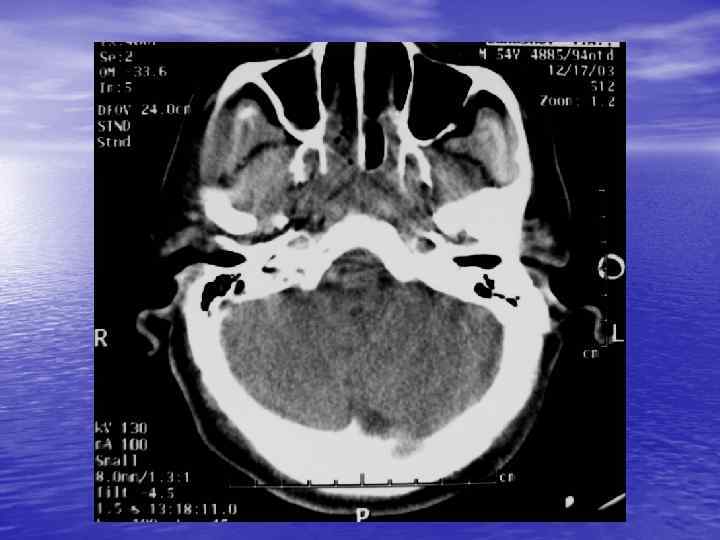

Преимущества спиральной КТ: ü Возможность проведения исследования с болюсным ü ü ü ü ü контрастированием Высокая разрешающая способность; Высокая скорость исследования; Получение высококачественных изображений костных структур; Возможность обследования всего тела; Возможность проведения исследования больных под наркозом; Возможность детальной оценки состояния крупных и периферических сосудов в условиях искусственного контрастирования; Высокая информативность метода при черепномозговых травмах в остром периоде; Ранняя диагностика ишемических и геморрагических инсультов; Метод выбора для диагностики заболеваний легких; Планирование лучевой терапии.

недостатками КТ являются: ü Высокая лучевая нагрузка на пациента. ü Необходимость применения ü ü водорастворимых йодсодержащих контрастных препаратов. Отсутствие визуализации спинного мозга. Затруднение визуализации задней черепной ямки, краниовертебрального перехода.